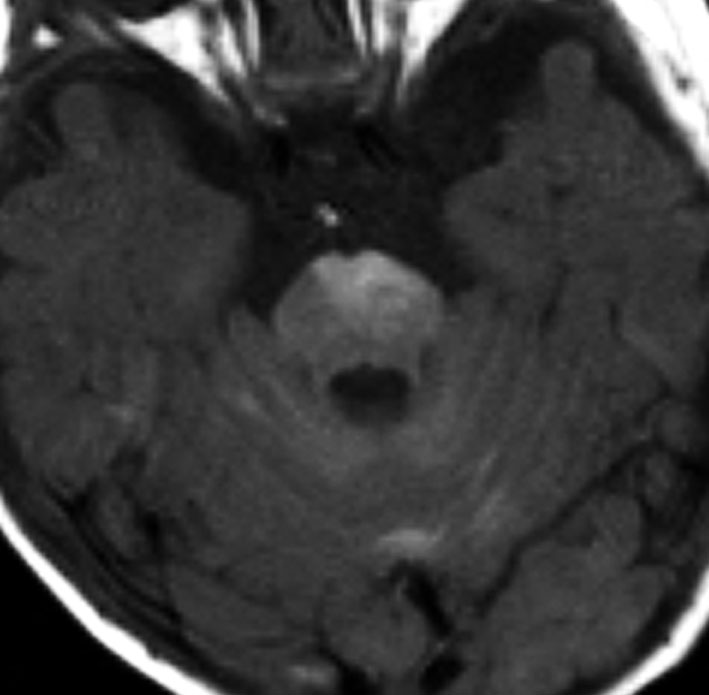

年長児例でけいれん発作と水頭症で発症した子どもです。中央の画像に見えるように,脳幹部の周囲が線状に白く増強されています。頭頂部にはゴロンとした腫瘤形成があり,これは悪性黒色腫 メラノーマだと考えられます。